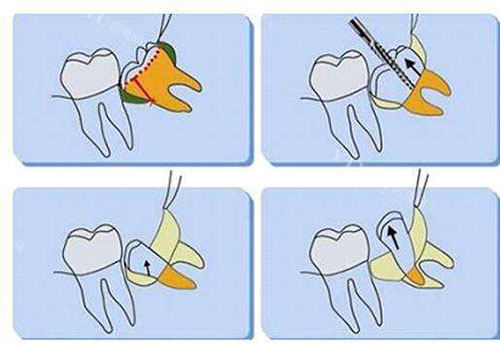

2. 阻生智齿(700-2500元起)

垂直阻生:600-1500元起

需切开牙龈暴露牙冠,手术时间约30分钟。某连锁品牌对垂直阻生智齿收费1000-1500元起。

水平阻生/倒置阻生:1500-2500元起

需去骨分牙的复杂手术,某综合医院口腔科对完全埋伏的水平阻生智齿收费可达2200起元。

特殊病例:

天津某高端诊所对"下颌近中阻生智齿(牙冠紧贴邻牙)"采用超声骨刀小创口技术,收费高达2500元,但术后肿胀率降低60%。

3. 技术设备成本

传统拔牙:200-800元起

小创口超声骨刀:加收500-1000元起

某医院对比数据显示:超声骨刀术后疼痛指数降低42%,但单次使用成本超2000元。